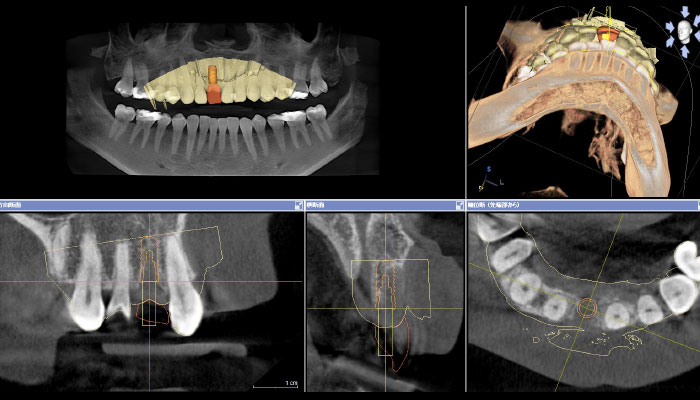

CT画像と口腔内スキャナーでスキャンした3D画像を重ね合わせて、最善のポジションにプランニングを行ったうえで、サージカルガイドの製作を依頼しました。 -

4.ガイデッドサージェリー

ガイデッドサージェリー(ガイド手術)中の動画はビデオで記録します。

インプラントの取り付けるジルコニアの義歯は、裏側にねじ固定のホールが来るように、正確なポジションにインプラントが埋入されています。

インプラントの埋入位置はパーフェクトです。